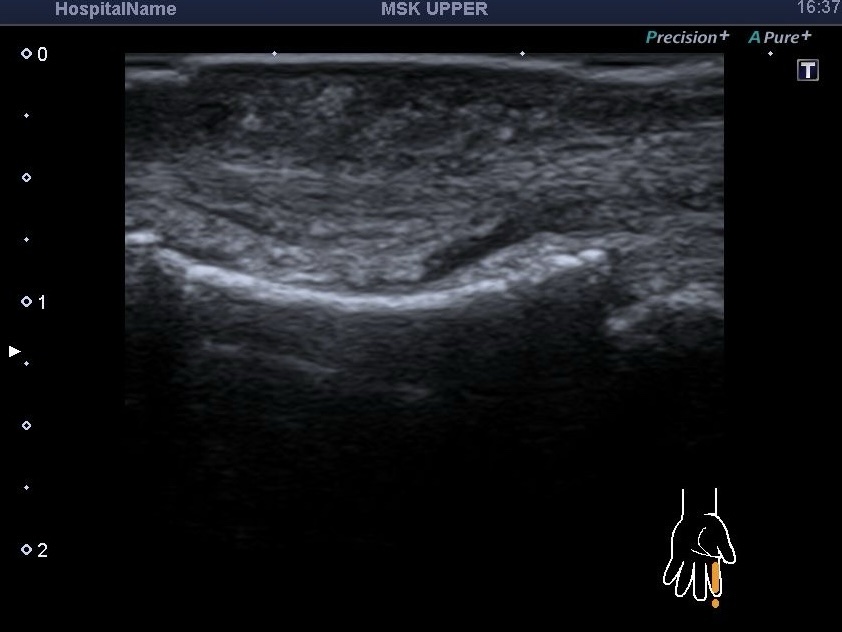

УЗД нервів та м’яких тканин. Якщо Ви думаєте, що дослідження нервів та м’яких тканин легко, то хочемо Вас розчарувати. Щоб...

УЗД нервів при травмах. Патологія периферичних нервів може бути розділена на дві великі групи: травматичні та нетравматичні ушкодження. Травматичні ушкодження...

В нашому кабінеті УЗД Medicine Group проводять багато видів УЗД, але можливо не всі чули про УЗД нервів .Це дослідження досить не...